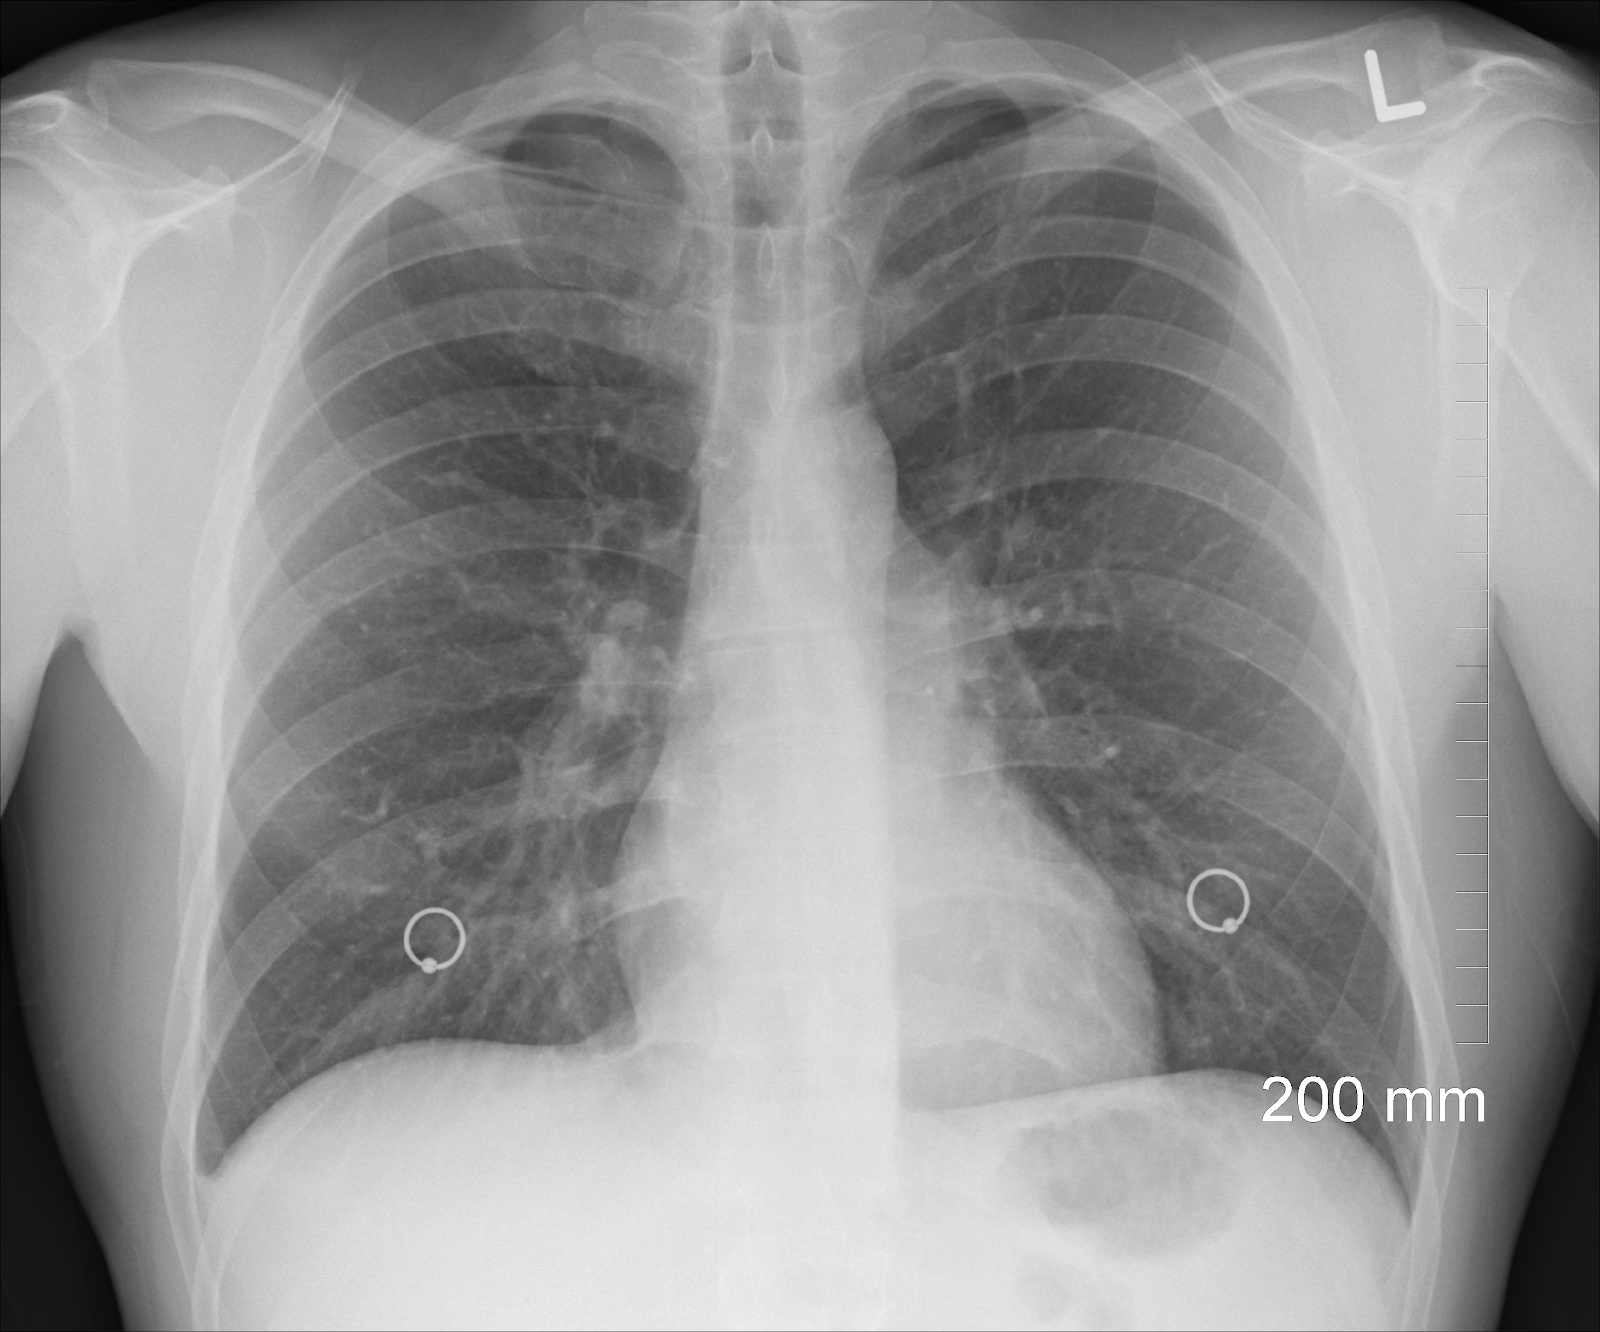

Lung Cancer XRay Photos — Examples of Different Types of Results

Lung cancer CXR Radiology at St. Vincent's University Hospital How Accurate Is Chest X-Ray For Lung Cancer You may be asked to have a blood test to rule out some of the possible causes of your symptoms, such as a chest infection. However, it’s possible that the tissue collected can be insufficient. Coughing up even a small amount of blood. Imaging tests are usually where the process begins, starting with a. The most accurate way to diagnose. How Accurate Is Chest X-Ray For Lung Cancer.